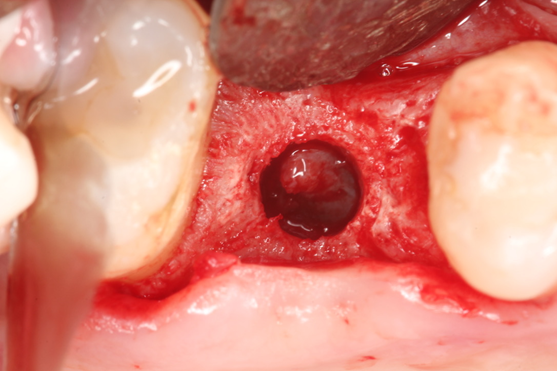

A paciente retornou após seis meses demonstrando clinicamente aspecto de mucosa queratinizada no rebordo alveolar (Figura 8) e, após abertura de retalho, vimos um rebordo ósseo saudável, com ligeira perda de espessura vestibular (Figura 9). A imagem tomográfica e a radiografia periapical sugerem formação de mais de 4 mm de altura óssea, além de ausência de sinusopatia (Figura 10), o que favorece a utilização do CAS Kit Osstem. Foi feita a fresagem cuidadosa com fresas CAS, promovendo o rompimento da cortical do seio maxilar, sem qualquer injúria à mucosa sinusal (Figura 11). Com o sistema de pressão hidráulica de injeção de soro fisiológico (Figura 12), foi realizada a elevação da mucosa e, em seguida, este espaço produzido foi preenchido com enxerto ósseo bovino (Figura 13).